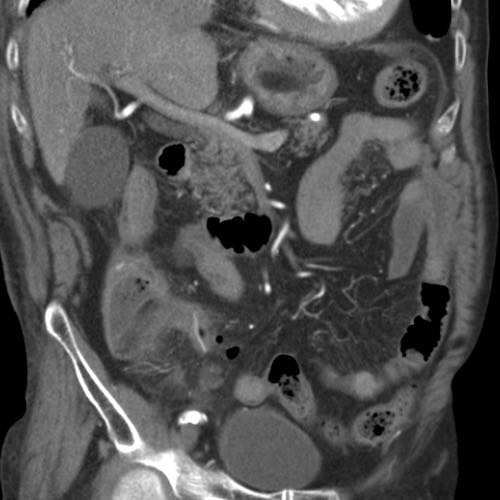

Bệnh nhân nữ 74 tuổi nhập viện với đau bụng dưới sâu kéo dài 3 tuần. Xét nghiệm: bạch cầu 15, CRP 150. Bệnh nhân có tiền sử nhiều lần phẫu thuật phụ khoa.

CT được thực hiện và phát hiện một dị vật dạng xương, với cả hai đầu đều có vẻ xuyên thủng đại tràng sigma.

Siêu âm qua đường âm đạo xác nhận dị vật đi xuyên qua lòng đại tràng sigma, do đó có thể lấy dị vật qua nội soi đại tràng.

Trong quá trình nội soi, xương gà phải được bẻ làm hai phần để lấy ra an toàn. Bệnh nhân hồi phục tốt với sự hỗ trợ của kháng sinh.